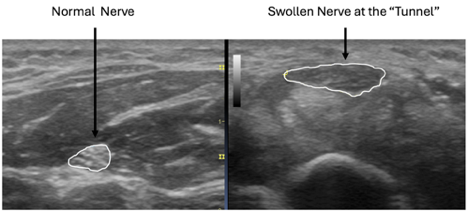

Before treatments can be proposed, however, the diagnosis needs to be clear. Ultrasound is among the most effective diagnostic tools, with images that have improved dramatically over the past decade. We can now see, measure, and evaluate the major nerves of the hands and feet. When a nerve is compressed, it appears swollen and inflamed. This swelling can’t be seen on X-rays and isn’t visible on typical MRI scans. These compressions most commonly occur in areas described as “tunnels,” including the wrist (carpal tunnel), the elbow (cubital tunnel), the forearm (radial tunnel), the foot (tarsal tunnel), and the hip (aponeurotic fascial tunnel). The names vary by location and are sometimes difficult to pronounce, but the effects on the nerve are the same. Compression causes the nerve to malfunction, resulting in numbness and pain. The following side-by-side ultrasound images show a cross-sectional scan of the median nerve in the wrist. The nerve is swollen, nearly double its size at the site of compression.